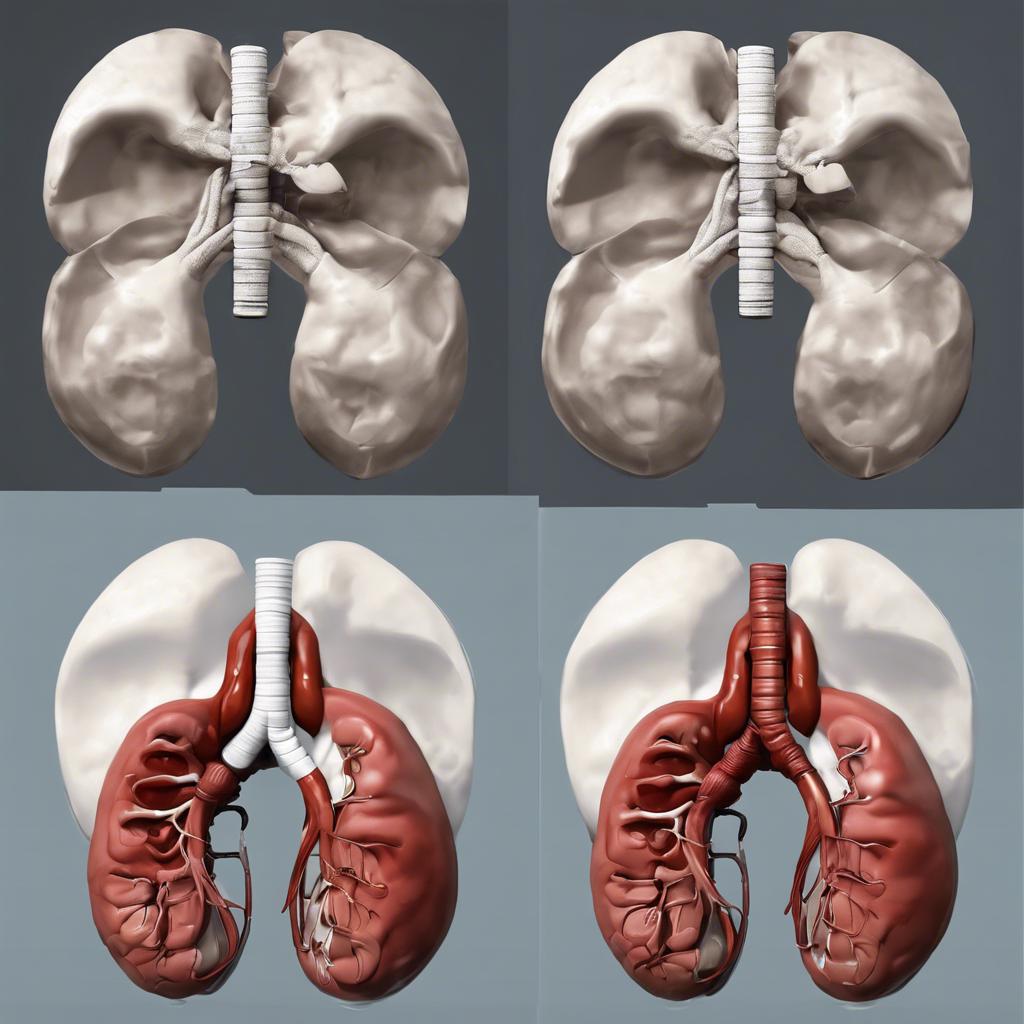

Wie funktioniert die Nierenfunktion und warum sind sie so wichtig für uns

Die Nieren sind echte Arbeitstiere in unserem Körper und sie spielen eine entscheidende Rolle, die oft unterschätzt wird. Wenn du einmal darüber nachdenkst, sie sind wie die ständige Wachposten; sie dokumentieren, was in deinem Körper passiert und sorgen dafür, dass alles im Gleichgewicht bleibt.

Hier sind einige der Hauptfunktionen der Nieren, die zeigen, wie wichtig sie für uns sind:

- Regulation des Flüssigkeitshaushalts: Die Nieren sorgen dafür, dass wir die richtige Menge an Wasser und Elektrolyten in unserem Körper halten. Zu viel oder zu wenig Wasser kann ernsthafte Probleme verursachen.

- Entgiftung: Sie filtern Abfallprodukte und Gifte aus dem Blut – das sind nicht nur überflüssige Stoffe, sondern auch toxische Substanzen.

- Blutdruckregulation: Durch die Kontrolle des Flüssigkeitshaushalts tragen die Nieren dazu bei, unseren Blutdruck stabil zu halten.

- Herstellung von Hormonen: Nieren produzieren wichtige Hormone wie Erythropoietin, das für die Bildung roter Blutkörperchen verantwortlich ist.

- Säure-Basen-Haushalt: Sie helfen, den pH-Wert des Blutes zu regulieren, was für unsere Gesundheit unerlässlich ist.

Wenn wir über die Nieren funktionale Beziehungen sehen, verstehen wir, dass sie nicht nur darin bestehen, einfach mit Filtration umzugehen. Vielmehr sind sie aktiv in die Aufrechterhaltung des inneren Gleichgewichts unseres Körpers eingebunden. Wenn wir uns bei einer survival-situationen vorstellen, können wir uns auf eine Vielzahl von Möglichkeiten vorbereiten, um die Nieren langfristig zu unterstützen.